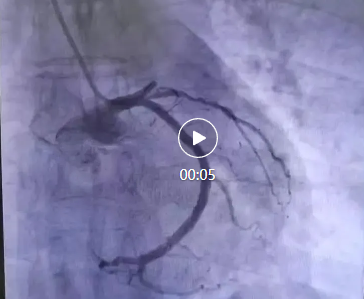

醫(yī)院立即啟動(dòng)了胸痛中心綠色通道。心血管內(nèi)科李桂武主任、劉興剛主任迅速到位,患者瀕臨崩潰的問道:“大夫,我能活么,孩子?jì)寢岆p目失明,還有倆孩子20歲不到,我要死了,這個(gè)家就完了”,李主任、劉主任握著患者的手堅(jiān)定地說道:“我們的目的不僅僅是讓您活著,還要讓您更有質(zhì)量的生活,所以你要堅(jiān)持,相信我們?!彪S即,李主任、劉主任為張先生進(jìn)行了冠狀動(dòng)脈造影,結(jié)果顯示,張先生的前降支近段完全閉塞,這是導(dǎo)致他胸痛的直接原因。李主任當(dāng)機(jī)立斷,決定進(jìn)行急診冠脈支架植入術(shù)。

手術(shù)過程非常順利。醫(yī)生通過導(dǎo)管將支架送至閉塞部位,成功開通了阻塞的血管,恢復(fù)了心肌的血液供應(yīng)。術(shù)后,張先生的胸痛明顯減輕,呼吸也逐漸平穩(wěn)。被轉(zhuǎn)入心臟重癥監(jiān)護(hù)室(CCU)進(jìn)行密切觀察。醫(yī)生為他制定了詳細(xì)的治療方案,包括抗血小板藥物、他汀類藥物、β受體阻滯劑等,以預(yù)防血栓再形成、穩(wěn)定斑塊并降低心臟負(fù)荷。!